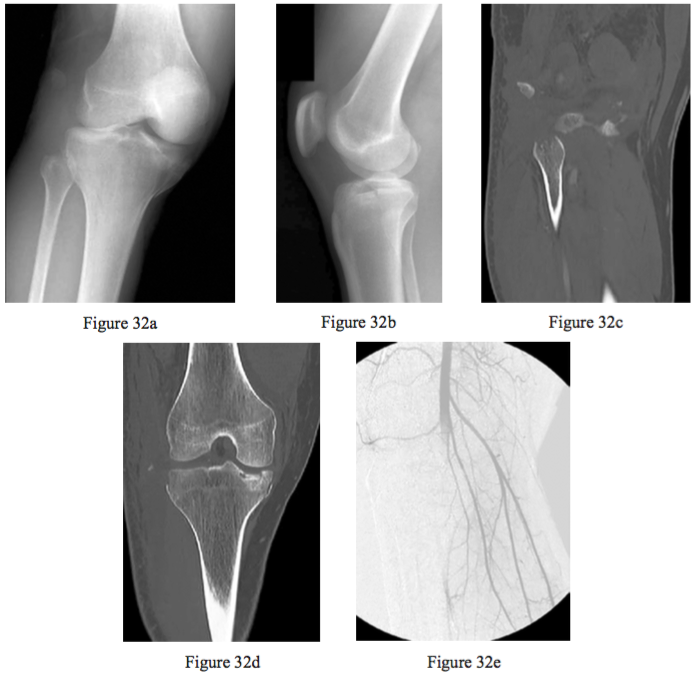

Figures 32a through 32e are the radiographs, CT scans, and arthroscopic view of a 26-year-old man who was hit by a car and sustained an injury to his right knee. Treatment of his injury should include

PREFERRED RESPONSE: 3 Revascularization of the leg, ORIF of the medial tibial plateau, and repair or reconstruction of the LCL and posterolateral corner.